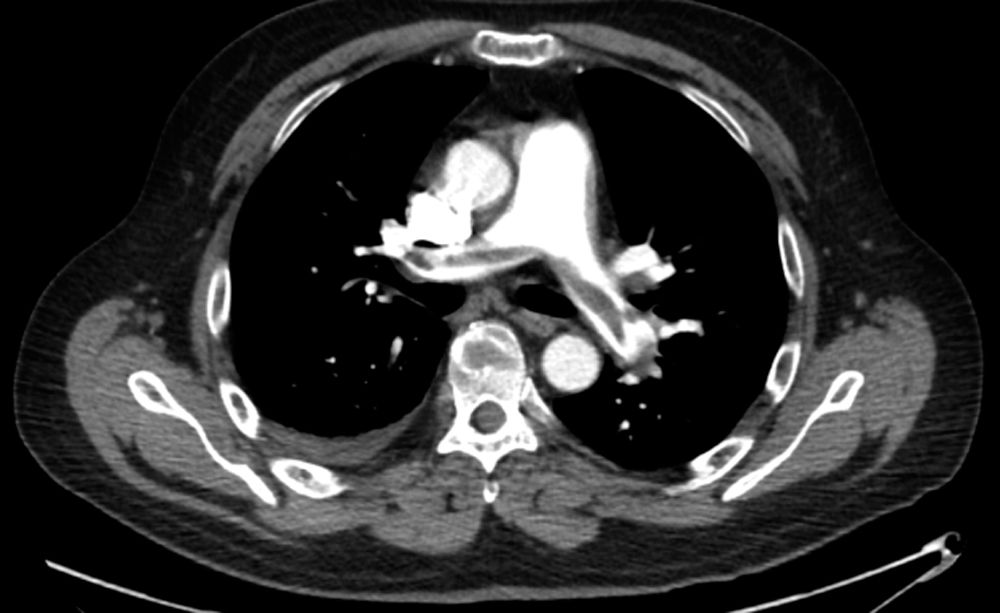

People may need to stay in the hospital and take . Shortness of breath, coughing up blood . The most common source of pulmonary emboli is deep vein thrombosis (dvt) in the lower limbs. Find out about the symptoms and treatments for this condition. A a pe is a blood clot or blood clots which have travelled to the lungs, usually from a deep vein thrombosis (dvt) of one of the deep veins . Difficulty catching breath, which may . A pulmonary embolism happens when a blood vessel in your lungs becomes blocked. Usually due to a blood clot that develops in another part of your body, . It is due to a blockage in a blood vessel in the lungs. Efthymios avgerinos sudden blockage of a major artery in your lung. What is pulmonary embolism (pe)?. Major risk factors for pe include: Pe is the term used to describe a blood clot (or multiple clots) that have become lodged in the blood vessels of the lung.